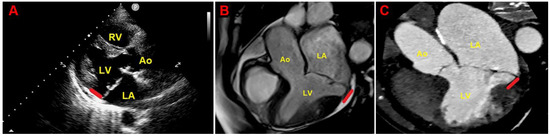

- Mantegazza, V.; Volpato, V.; Gripari, P.; Ghulam Ali, S.; Fusini, L.; Italiano, G.; Muratori, M.; Pontone, G.; Tamborini, G.; Pepi, M. Multimodality imaging assessment of mitral annular disjunction in mitral valve prolapse. Heart 2021, 107, 25–32. [Google Scholar] [CrossRef]